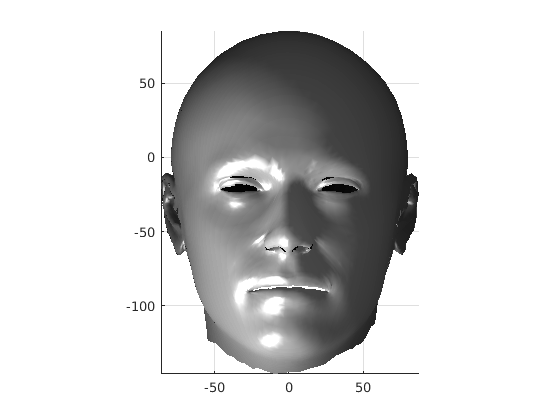

Toolsets to define normal appearance and therefore both assist with planning of surgery and define optimal outcomes from a range of surgical interventions are currently either crude or lacking. Therefore, the unit collected a large, high quality 3D image dataset of 1523 human heads. An example is given in Fig. 1 showing the 3D channel only on the left, and the 3D data with texture pasted on on the right. The data was collected over well-conserved demographics, and an age range of 1 to 89 years, see Fig. 2. The dataset was collected with the aim of developing a normal equivalent of the human cranium and face in order develop the tools to enhance patient experience following surgery. We plan to make the dataset publicly available in the near future.

7 Extension to 3D full head modelling

Using the ECN pose normalisation technique described in previous sections, we have built a 3D statistical model of the full head, including face and cranium, using the same 100 scans of adult males as we used in the cranial profile model described earlier. We employed a variant of a template morphing technique called Optimal-Step Non-rigid Iterative Closest Points (OSNR ICP) [11]. However, its application to the full human head is more difficult than with face only, due to the lack of well-defined landmarks for initial alignment over the cranial area.

The template mesh is then warped in a global affine sense, as shown in Fig. 27 to minimise the least-squares error between the two sets of landmarks, when the head scan is fixed in its canonical poose. After this initial stage, landmarks and pseudo-landmarks are used in the same way as any other mesh vertex, as they are potentially noisy, as seen in earlier results analysis. This contrasts with Amberg et al’s [11] approach where the influence of landmarks is gradually faded out.

Following this, OSNR ICP iterates over a set of decreasing mesh stiffnesses (typically 10), until the registration between the template and the scan is below some error or a maximum number of iterations is reached. Figure 28 shows a selection of template warp results. The template appears to be accurately warped onto the scan, at least in the normal direction of the surfaces, it is not possible to see error tangential to the surface. Furthermore, we have noted errors on some scans on the ears. To improve these we need a method of automatically landmarking the ears, which is an area for further work.

The first two modes of head variation are shown in figures 29 and 30. These include the cranial height / facial angle mode and the (almost) pure size mode, as seen in the sagittal profile model.